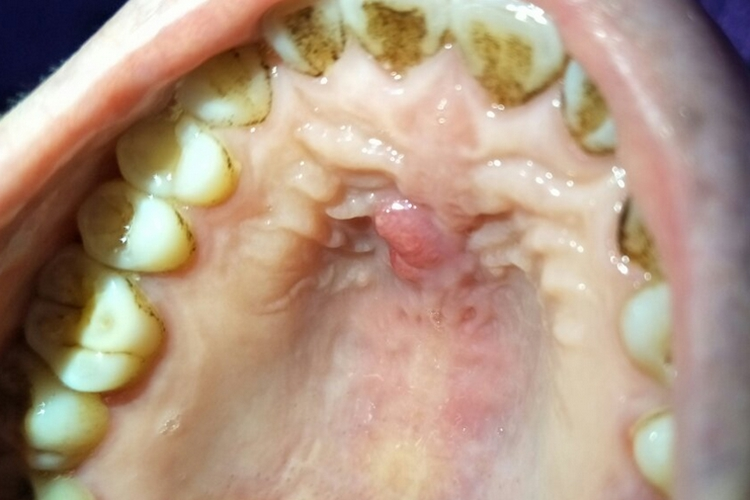

上腭有凸起的包,可能是口腔溃疡、黏液腺囊肿、根尖周脓肿、上腭肿瘤、骨隆突等引起。口腔溃疡用药物促进愈合,如果黏液腺囊肿较大,则选择手术治疗。

2、黏液腺囊肿:

- 上腭的小唾液腺导管阻塞,腺体分泌物潴留形成囊肿,表现为凸起的包,较小的囊肿可以先观察,如果囊肿较大或影响进食、说话,通常需要手术切除。

4、上腭肿瘤:

- 包括良性肿瘤和恶性肿瘤,肿瘤细胞异常增生形成凸起的包,通常需要进行病理检查以明确肿瘤的性质。良性肿瘤一般手术切除即可;恶性肿瘤可能需要综合手术、放疗、化疗等治疗方法。